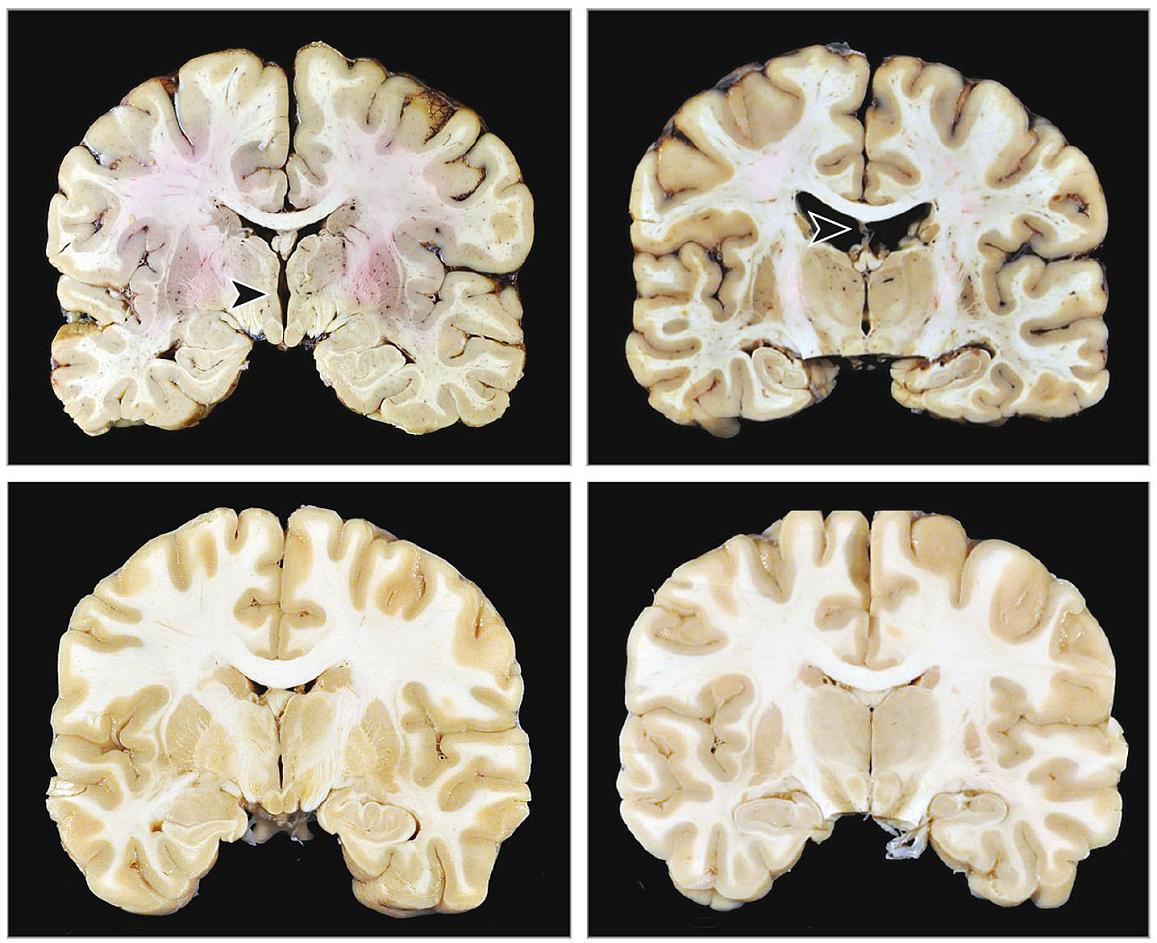

Nonconcussive head impacts are correlated with the presence and severity of CTE.

A study of 631 deceased American football players revealed that the odds of having CTE was related to the estimated number and strength of impacts to the head, but not related to the number of diagnosed, self-reported or family-estimated concussions.